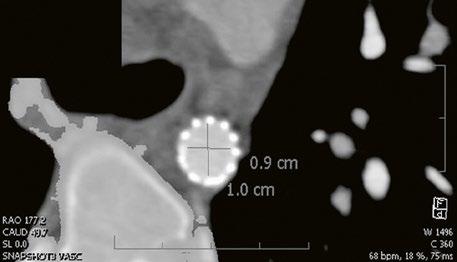

Supravalvární pulmonální stenóza a stenózy větví plicnice bývají součástí komplexních VSV (např. Fallotovy tetralogie) nebo syndromů (Williamsův syndrom, syndrom Noonanové, syndrom vrozené rubeoly, Alagillův syndrom aj.) (Obr. 45.39). Získané stenózy větví plicnice, ale i úplný uzávěr větve plicnice můžeme vidět po spojkových operacích podle BlalockaTaussigové (Obr. 45.40, Obr. 45.41). Pro zobrazení supravalvárních a periferních stenóz plicnice je optimální CT angiografie (Obr. 45.40, Obr. 45.41, Obr. 45.42, Obr. 45.43).

Obr. 45.40 CT angiografie, 8mm stenóza a deformace levé větve plicnice (šipka) po spojkové operaci podle BlalockaTaussigové v dětství LPA – levá větev plicnice, PA – kmen plicnice, RPA – pravá větev plicnice